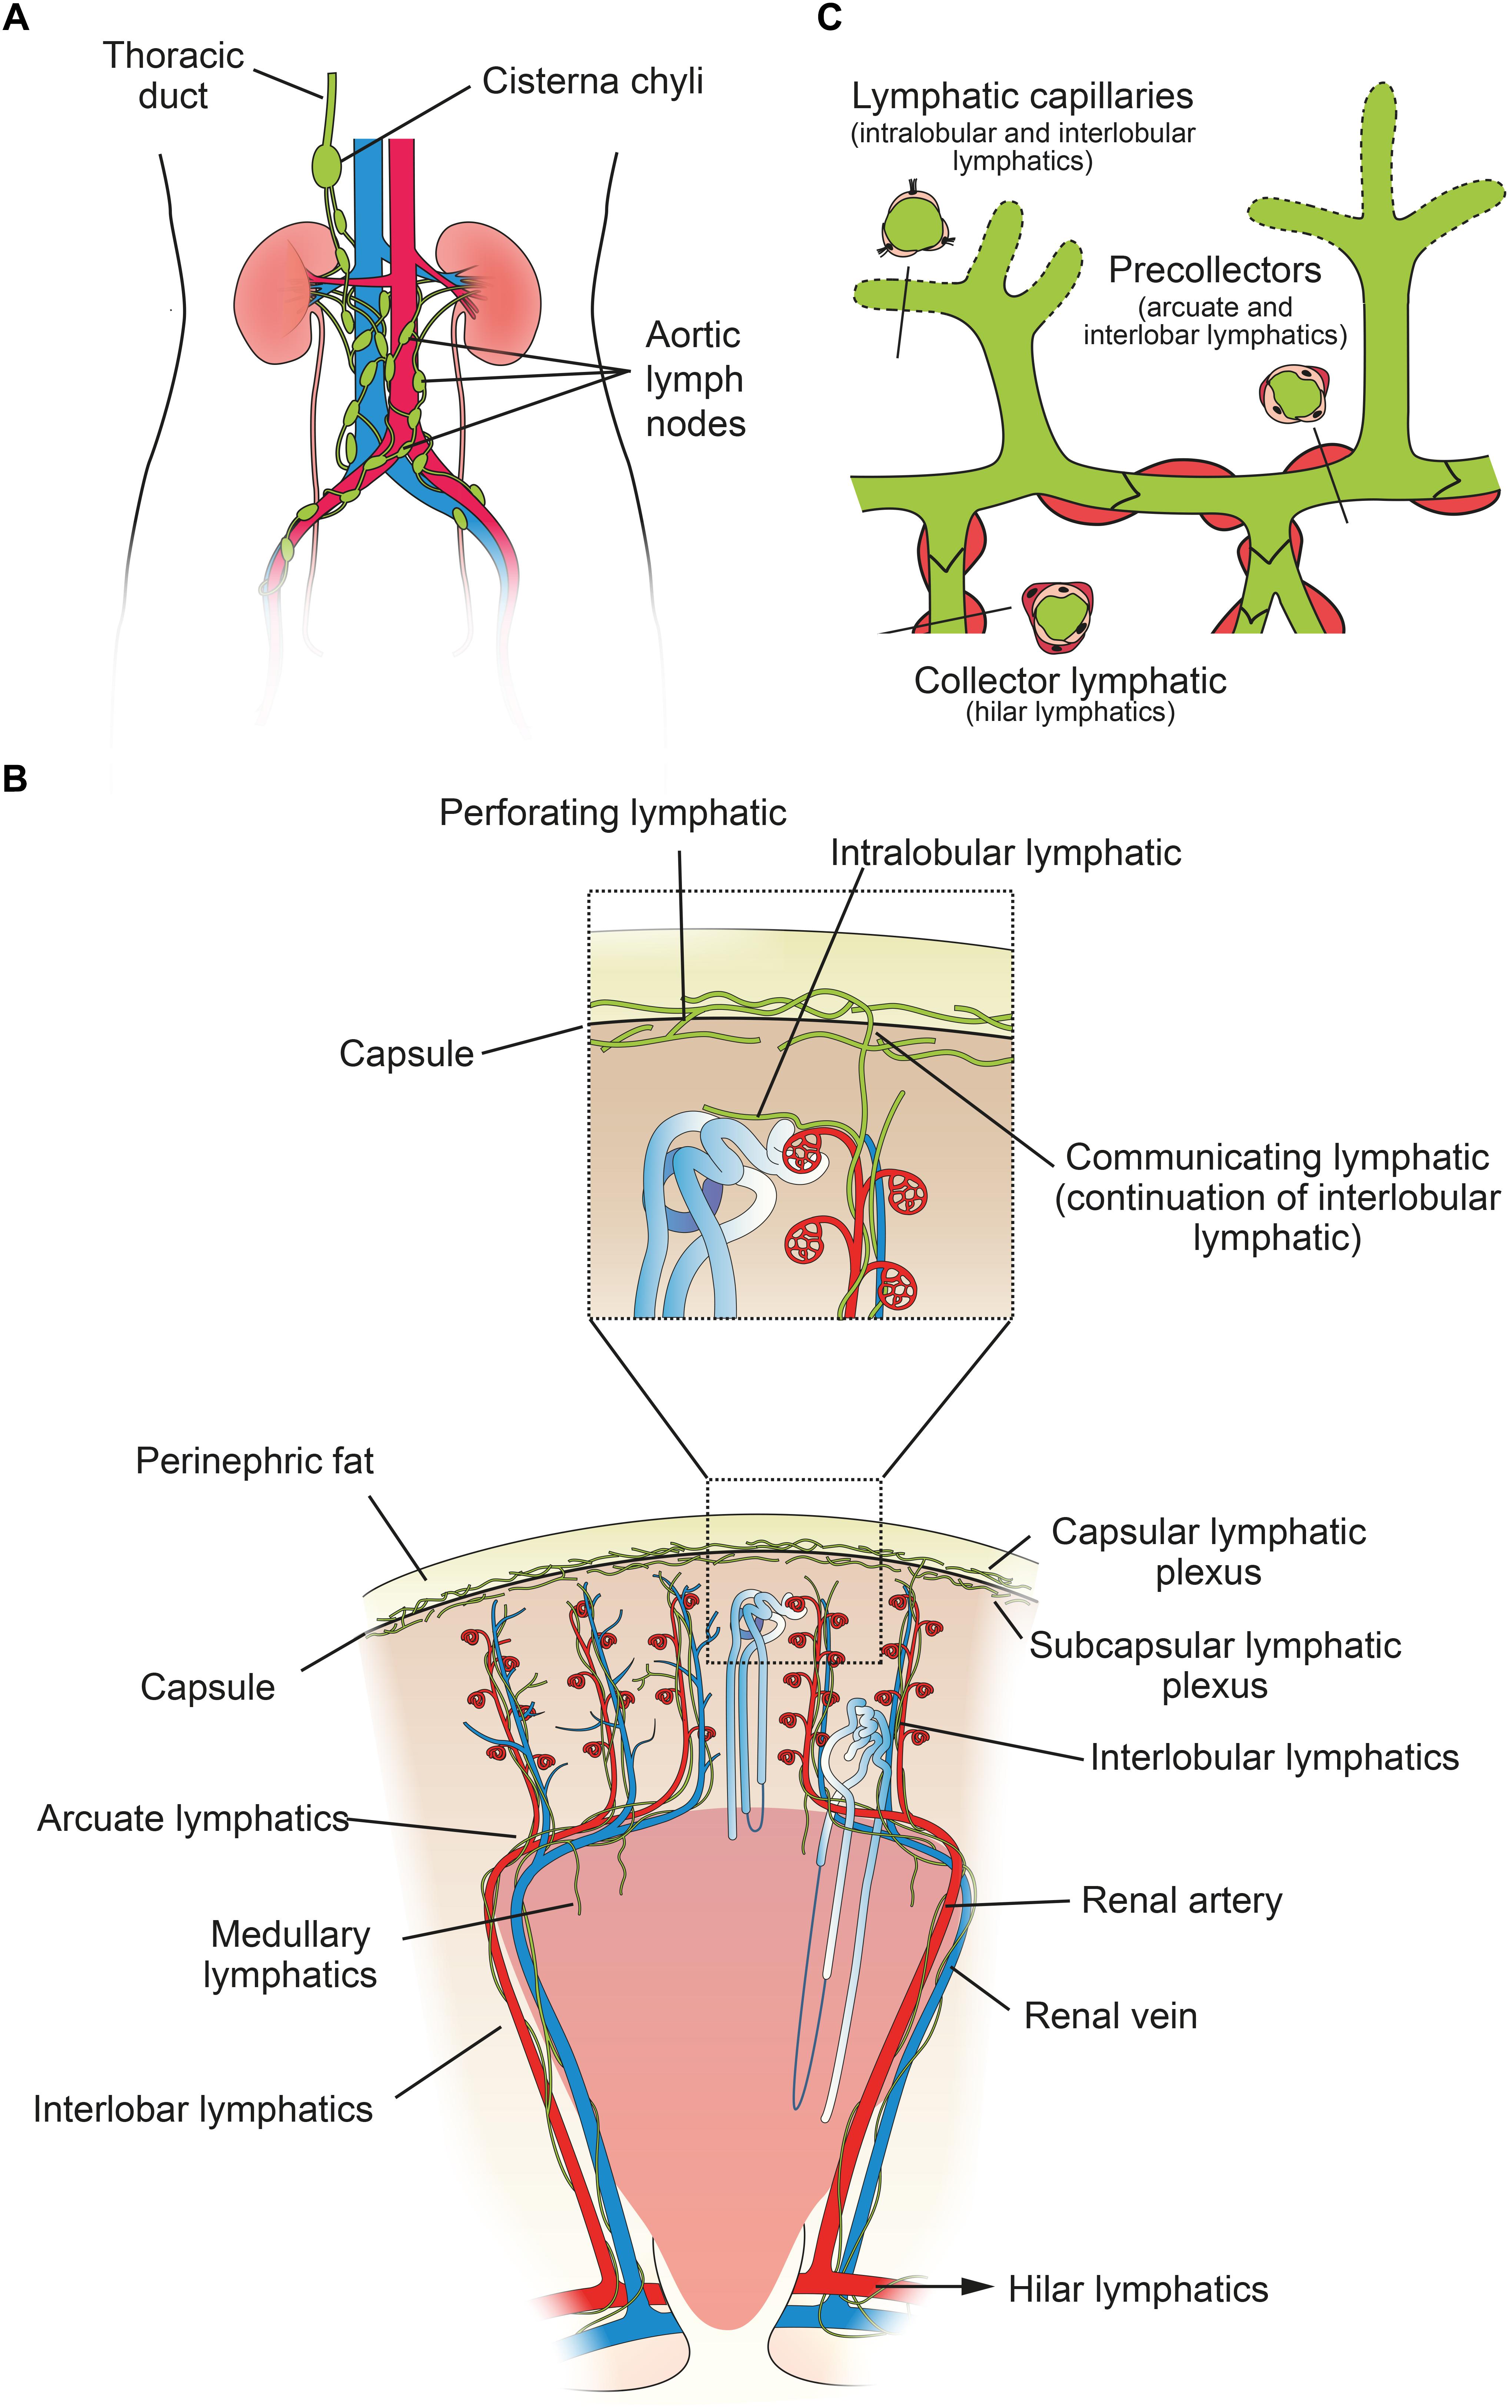

Frontiers Renal Lymphatics Anatomy Physiology And

Frontiers Renal Lymphatics Anatomy Physiology And